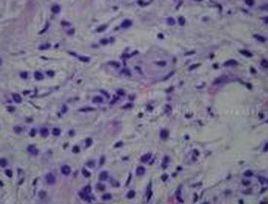

痣細胞3.惡性黑素瘤常不對稱,邊界不清楚,邊緣不光滑,顏色不均勻,發展迅速,容易破潰、出血,可形成不規則瘢痕,組織學顯示痣細胞異型。中心暗點以及屈光度的改變 是脈絡膜惡性黑色素瘤所表現出來的一種重要症狀。